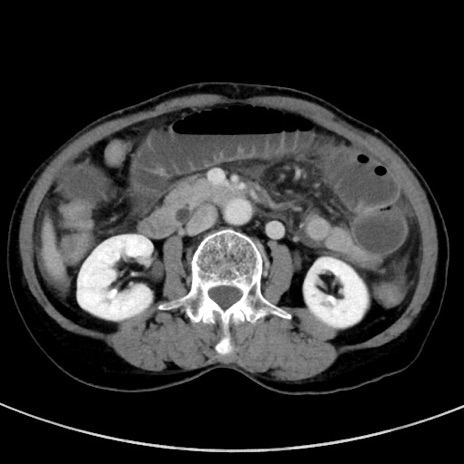

症例23(横断像)

【症例】70歳代女性

【主訴】下腹部痛・嘔吐

【現病歴】2日前より腹痛あり。昨日嘔吐あり。症状改善しないため来院。

【既往歴】胃GISTに対して胃部分切除後。

【身体所見】BT 37.1℃、BP 128/77mmHg、腹部:平坦・軟、下腹部に圧痛あり。

【データ】WBC 10200、CRP 0.31